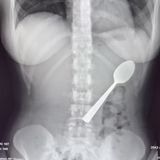

Osmadvacetiletá Belgičanka Reymy Amelinckx se podělila se světem o kuriózní nehodu, která se jí přihodila při jedení jogurtu. Omylem spolkla 17 cm dlouhou lžičku a málem se s ní zadusila. Zdá se vám, že taková věc snad ani není možná? No, zjevně je možné všechno.

Reymy seděla na gauči a jedla jogurt. Lžičku si dala do pusy, aby měla volné ruce a mohla datlovat na telefonu. V tom se její pes Marley rozhodl, že na ni skočí. Brunetku natolik polekal, že zaklonila hlavu a než se nadála, lžička jí klouzala do krku.

Na pohotovosti jí řekli, že je lžíce moc velká a bude muset počkat, až jí naplánují gastroskopii, během které jí vytáhnou. Reymy se odebrala zpět domů, ale v noci se moc nevyspala. Cítila, jak jí lžíce v těle putuje, občas jí píchala do žeber. Reymy byla vystrašená, nafouklá a bylo jí nevolno.

O dva dny později jí pod lokální anestezií vytáhli lžíci krkem ven. V žaludku ji museli otočit, a tak došlo ke drobnému poranění. Belgičanka sice označila zákrok za nepříjemný, ale nesmírně se jí ulevilo, když jí lžíci z žaludku vytáhli.